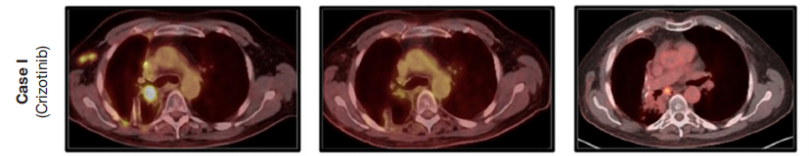

- 精准医学带来生存奇迹!新型抗癌药物让四期肺癌患者成功摆脱癌症!